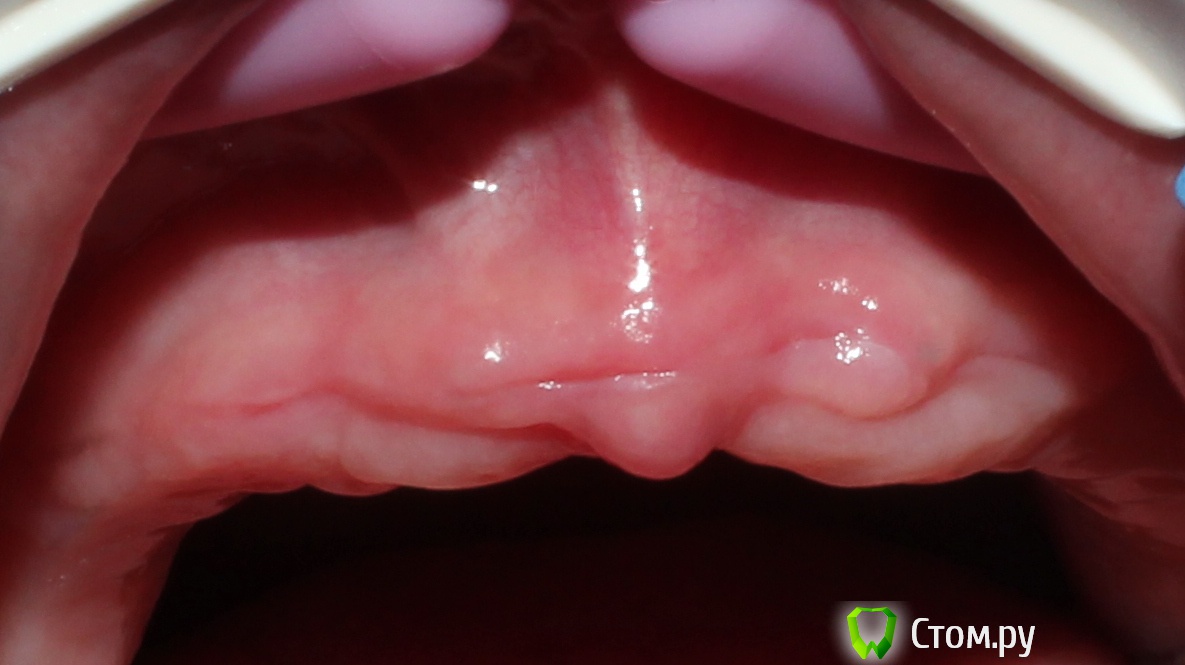

artem29 Опубликовано 19 октября, 2014 Поделиться Опубликовано 19 октября, 2014 (изменено) Уважаемые доктора, поделитесь, пожалуйста, опытом. Есть пациентка, возраст после 40 лет. Желает избавится от частично съёмных протезов, заменить их несъёмными. КТ будет чуть позже.Я (как хирург) могу предположить, что установка имплантатов в позиции 5-5 и 2-2, ждём пока интегрируют и затем балочная конструкция.Перед установкой имплантатов провести синуслифтинг, либо совместить аугментацию и установку имплантатов (решится в процессе синуслифтинга). Слева по типу латерального окна, а справа, возможно, достаточно будет и закрытого. Какую бы тактику спланировали вы на верхней и на нижней челюсти и какой длины имплантаты для верхней челюсти взяли?система: Dentium: SuperLine. Заранее всем благодарен. Изменено 19 октября, 2014 пользователем artem29 Ссылка на комментарий